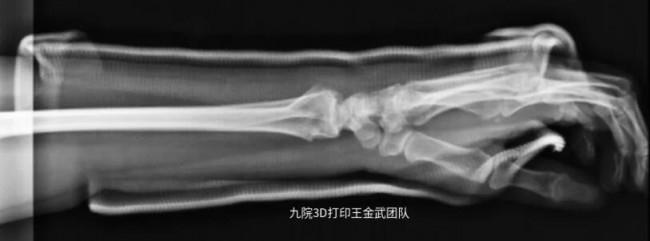

患者左臂桡骨远端骨折,骨折固定后佩戴3D打印固定支具辅助恢复情况良好。

▲骨折后X光